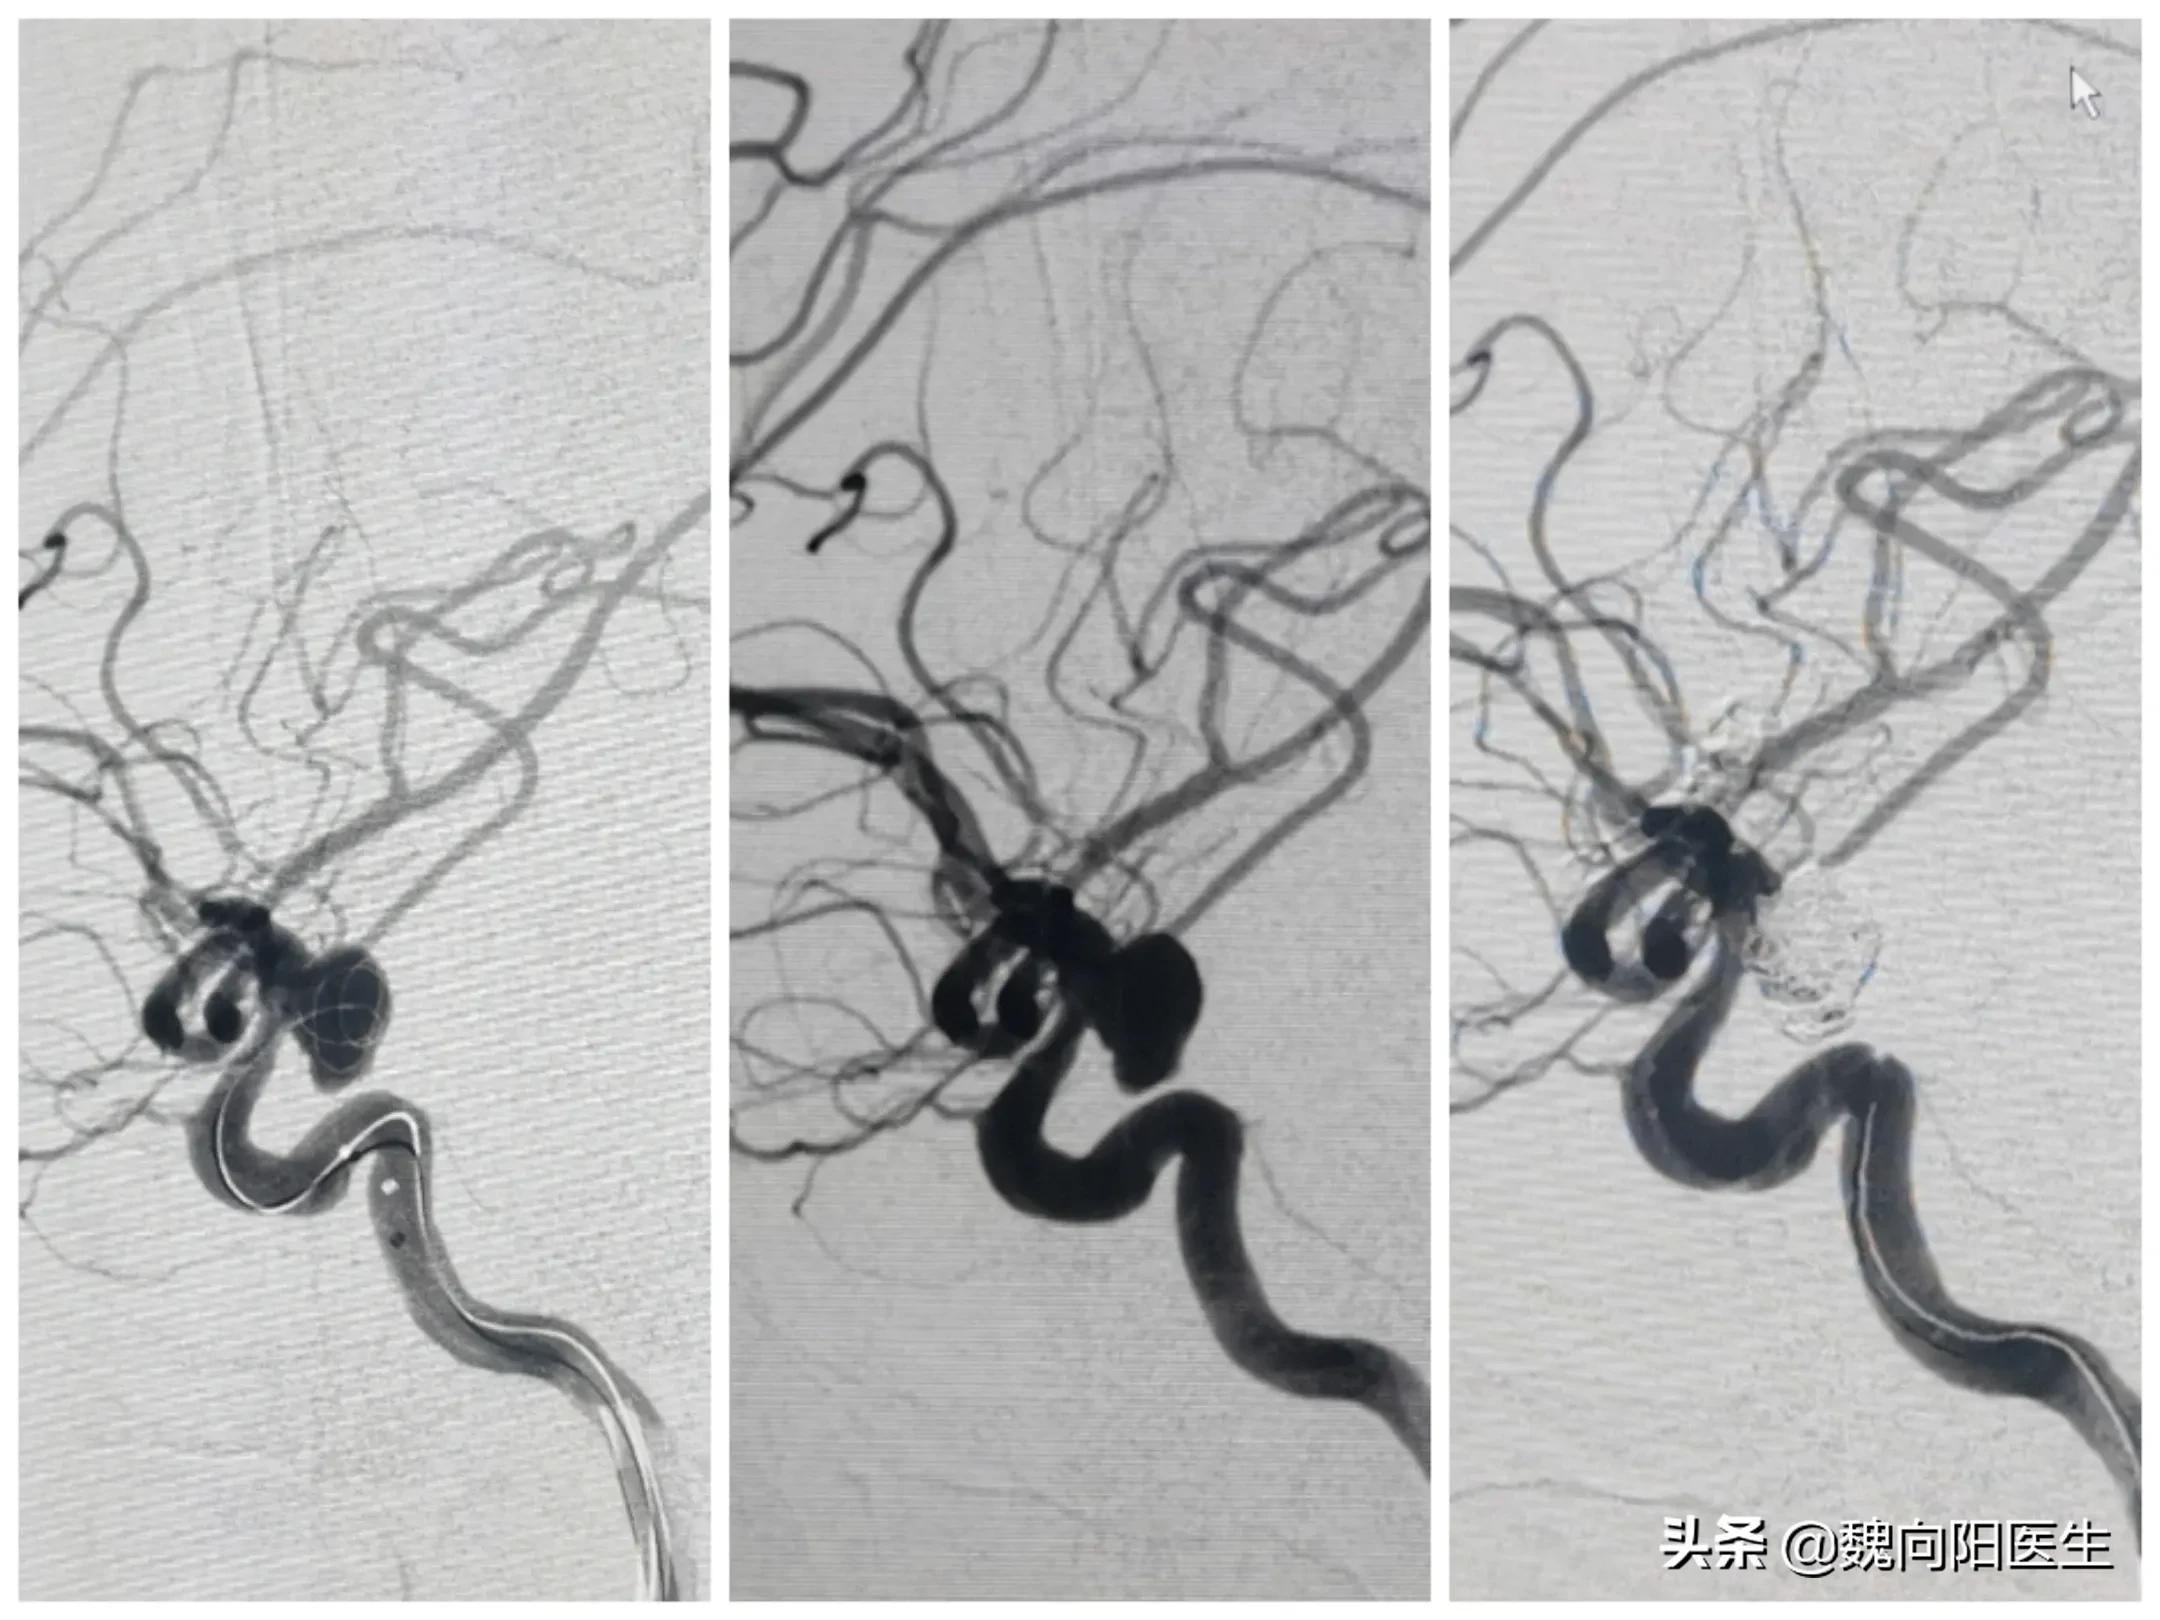

当送至我院后,再次复查头CT发现:“患者蛛网膜下腔出血较前增多,伴双侧侧脑室扩大”,且患者和昏迷状态更加严重,出现了呼吸困难情况,在急诊立即给予经口气管插管术,给予呼吸机辅助通气治疗。患者目前的意识状态逐渐加重,考虑是患者急性蛛网膜下腔出血并发急性脑积水导致,且脑积水情况进行性加重,立即给予侧脑室穿刺引流,改善脑室积水。诊断周某是自发性蛛网膜下腔出血,不排除患者出血原因是颅内动脉瘤破裂导致,因此建议立即行脑血管造影检查,明确发病原因,并给予有针对性的治疗。经患者家属同意后,立即联系介入导管室,给予全麻下脑血管造影发现:“小脑后下动脉动脉瘤”,经过分析考虑该动脉瘤为责任病灶,如果不处理该动脉瘤,则第二次出血风险高,且一旦再次出血后症状会更加严重,甚至危及生命。

再次与患者家属沟通后,给予经导管颅内动脉瘤栓塞治疗。